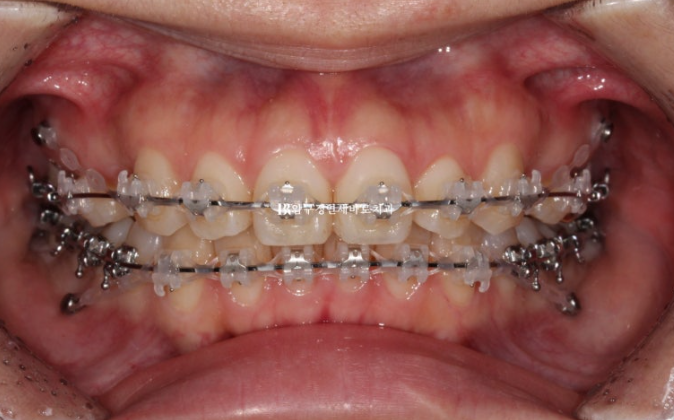

23.11

The procedure was carried out after placing mini-screws.

24.03

About half of the extraction space remained at this point.